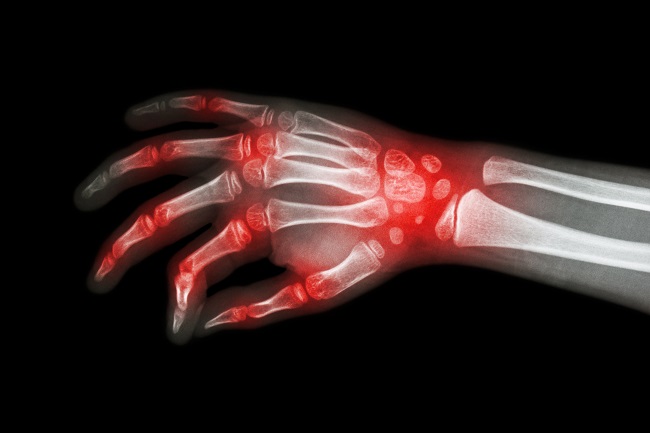

Gejala yang dialami oleh anak-anak yang menderita JIA tidak hanya melibatkan sistem muskuloskeletal, tetapi juga melibatkan sistem organ yang lain. Beberapa sistem organ yang mengalami gangguan antara lain sistem integumen, limfatik, hepar, limpa, bahkan mata. Gambaran dari kondisi JIA berbeda bergantung pada subtipe dari JIA.[3,4]

Diagnosis dari JIA merupakan diagnosis eksklusi. Oleh sebab itu, perlu dilakukan pemeriksaan menyeluruh untuk menegakkan diagnosis. Pemeriksaan menyeluruh meliputi anamnesis, pemeriksaan fisik, dan pemeriksaan penunjang. Saat ini terdapat klasifikasi yang digunakan untuk membantu menegakkan diagnosis JIA.[1,5]